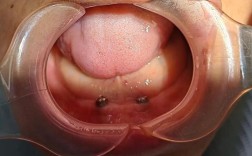

| 种植手术 | 局部麻醉后,在牙槽骨植入种植体,微创技术(如即刻种植)可缩短手术时间,缝合伤口 | 30-90分钟 | 术后24小时内避免刷牙、漱口,遵医嘱服用抗生素 |

A:种牙时间因人而异,若患者牙槽骨条件良好,无需植骨,可选择“即刻种植”,即拔牙后立即植入种植体,结合“即刻负重”技术,当天安装临时牙冠,满足基本美观和咀嚼需求,但临时牙冠需3-6个月后更换为永久牙冠;若骨量不足,需先植骨,待骨结合(3-6个月)后再种植,总时长约6-9个月,金琴口腔会根据CBCT检查结果,评估是否适合即刻种植,制定个性化时间方案。